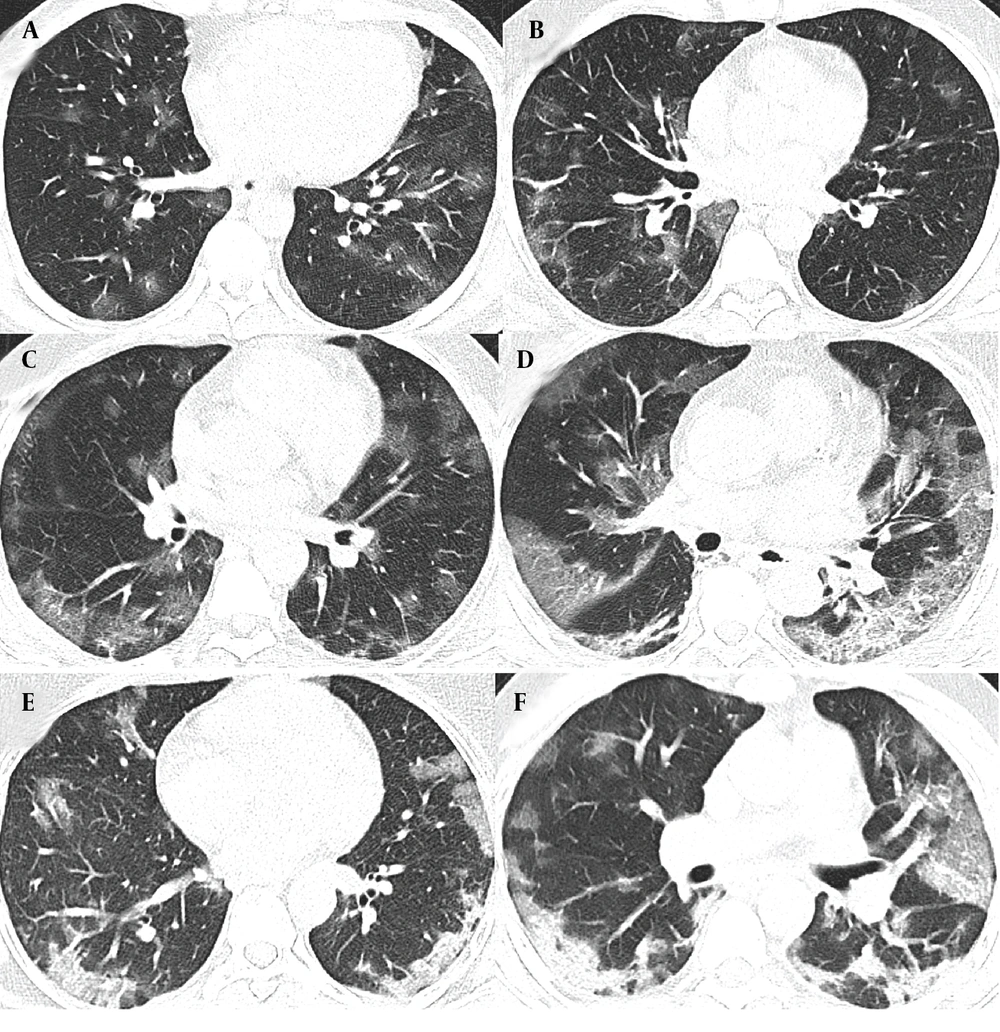

The characteristics of COVID-19 patients with oxygen saturation levels below and above 90% were examined in two distinct cohorts, each with training and validation groups. The first cohort includes patients with oxygen saturation below 90%, comprising 224 in the training group and 96 in the validation group. The second cohort involves patients with oxygen saturation equal to or above 90%, with 482 in the training group and 206 in the validation group. A detailed breakdown of clinical characteristics, biological measures, symptoms, and CT features is provided in Appendix 12, 13 and 14 in the Supplementary File. Figure 2 depicts the typical progression of lung damage in COVID-19, from ground-glass opacity to consolidation, reflecting the increasing severity of the disease. Appendix 15 in the Supplementary File provides a complete list of features selected in each model by the top-performing classifier, along with their importance and stability scores.

A and B, The radiographic progression of lung involvement in COVID-19 pneumonia, beginning with ground-glass opacity (GGO), an early radiographic finding representing alveolar damage and fluid accumulation; C, As the disease advances, GGO may increase in distribution, exhibiting peripheral predominance; C and D, The crazy paving pattern, characterized by thickened interlobular septa superimposed on ground-glass opacity, indicates deeper lung parenchyma involvement; E and F, Further progression leads to consolidation; where dense opacities obscure the underlying vasculature, signaling severe alveolar damage.